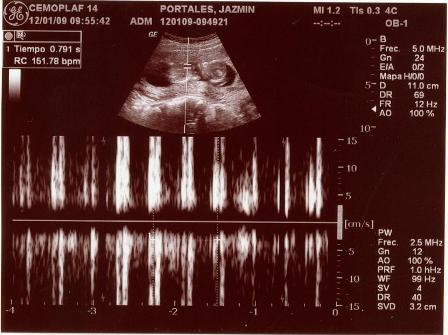

Fotos del 19 En 2009:

Informe:

Embarazo con feto de 13 semanas 4 días +/- 1 semana.

LCF: 151 lpm

Movimientos: Activos normales

Impresión: Feto único, vivo con movimientos normales y actividad cardiaca normal. OCI cerrado.